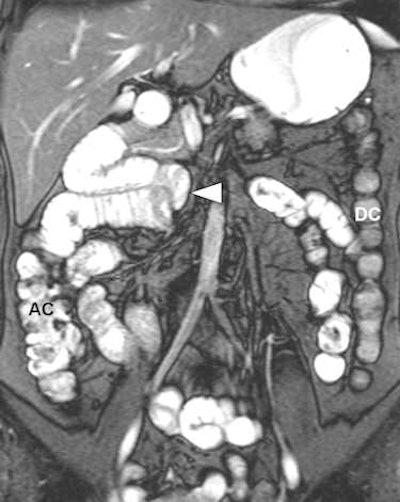

A 37-year-old female patient presented with chronic abdominal pain and was suspected of having irritable bowel syndrome. MR enteroclysis coronal fat-saturated true-FISP image demonstrates the duodenojejunal junction and proximal jejunum loops located on the right-hand side of the abdomen (arrowhead) and the normal position of the ascending colon (AC) and descending colon (DC). All images courtesy of Dr. Giedre Kavaliauskiene.There seems to be no major differences in accuracy between ultrasound, CT, scintigraphy and MRI in diagnosing inflammatory bowel disease, so it is wise to use a noninvasive technique without radiation exposure to detect small bowel lesions in patients with Crohn's disease, wrote Kavaliauskiene in an article published online on 13 July by Insights into Imaging. Important advantages of MRI are the unrestricted overview, easy comparison between examinations, and improved communication of results to the referring physician. Therefore, MRI is the technique of choice in many centers.